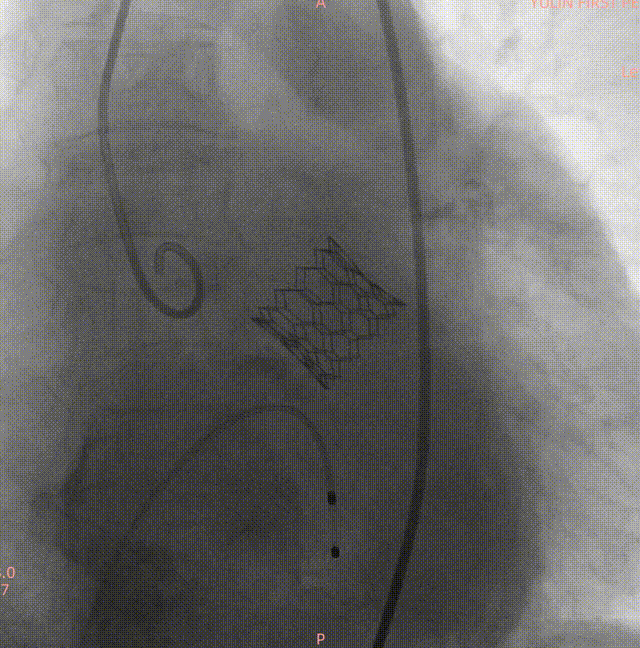

释放后造影示瓣膜位置理想,形态良好

手术过程

通过术前精准评估,患者在全麻下行TAVR手术,DSA和食道超声双重引导,通过右侧股动脉建立工作路径,沿加硬导丝送入19mm*40mm球囊预扩张主动脉瓣,预扩时双侧冠脉显影良好。退出预扩张球囊后,利用可调弯输送器送入23#RENATUS瓣膜至升主动脉,猪尾巴导管再次造影确认位置。将23#RENATUS瓣膜顺利跨瓣,精准定位,4ATM精确释放,退出输送系统再次行主动脉根部造影,示瓣膜膨胀充分,无瓣口反流,无瓣周漏,冠脉血流正常,再次测主动脉根部压力及左心室压力,术后即刻平均跨瓣压差降至3.33mmHg,超声示术后峰值流速降至0.91m/s。瓣膜释放位置理想、形态及功能良好,瓣叶启闭良好,无外周血管损伤。

术中影像

主动脉根部造影

19mm球囊预扩

瓣膜定位

23#Renatus瓣膜释放中再次造影定位